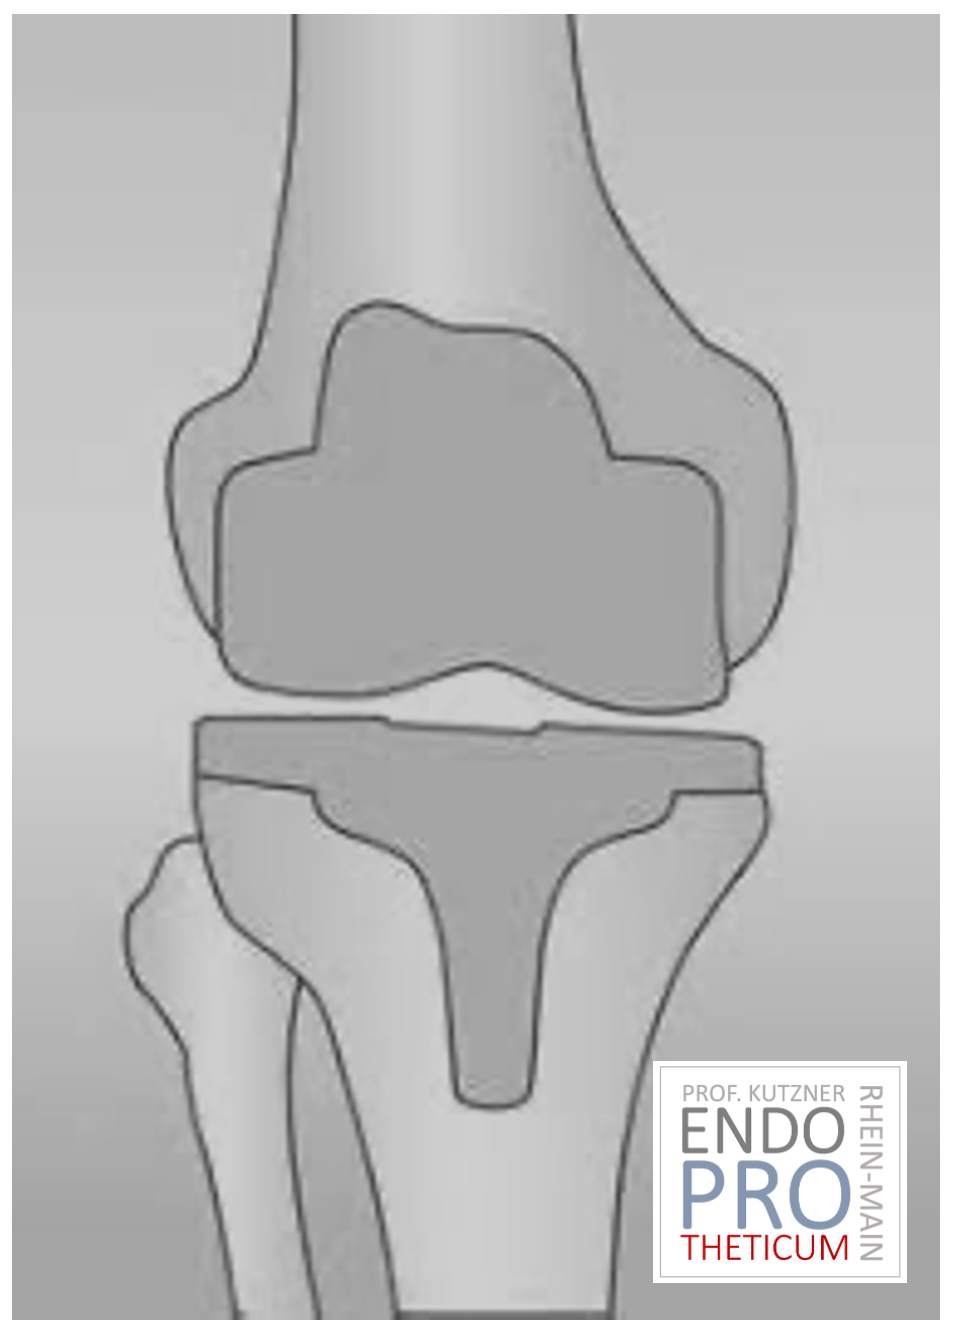

PTG (ARTICULATION ARTIFICIELLE DU GENOU)

L’articulation artificielle du genou remplace la surface cartilagineuse détruite par l’arthrose. L'os sous-jacent du fémur et de la tête tibiale reste intact. Certains comparent une articulation artificielle moderne du genou à un couronnement de dent ; le terme exact est ce qu'on appelle le resurfaçage bicondylien. Entre les nouvelles surfaces sur la partie supérieure et inférieure de la jambe se trouve ce que l'on appelle une incrustation en plastique blanc spécialement durci, qui peut être vue sur l'image radiographique comme la distance entre les pièces métalliques.